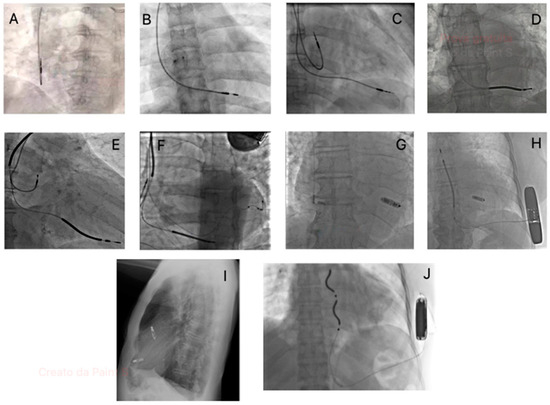

2.2. Venous Obstruction Syndrome

- Czajkowski, M.; Polewczyk, A.; Jacheć, W.; Kosior, J.; Nowosielecka, D.; Tułecki, Ł.; Stefańczyk, P.; Kutarski, A. Multilevel Venous Obstruction in Patients with Cardiac Implantable Electronic Devices. Medicina 2024, 60, 336. [Google Scholar] [CrossRef]

- Zimetbaum, P.; Carroll, B.J.; Locke, A.H.; Secemsky, E.; Schermerhorn, M. Lead-Related Venous Obstruction in Patients with Implanted Cardiac Devices: JACC Review Topic of the Week. J. Am. Coll. Cardiol. 2022, 79, 299–308. [Google Scholar] [CrossRef] [PubMed]

- Czajkowski, M.; Polewczyk, A.; Jacheć, W.; Nowosielecka, D.; Tułecki, Ł.; Stefańczyk, P.; Kutarski, A. How does a CIED presence influence chances and safety of haemodialysis access? Conclusions from over 3000 thoracic venografies. Clin. Physiol. Funct. Imaging 2023, 43, 47–57. [Google Scholar] [CrossRef]

- Gabriels, J.; Chang, D.; Maytin, M.; Tadros, T.; John, R.M.; Sobieszczyk, P.; Eisenhauer, A.; Epstein, L.M. Percutaneous management of superior vena cava syndrome in patients with cardiovascular implantable electronic devices. Heart Rhythm 2021, 18, 392–398. [Google Scholar] [CrossRef] [PubMed]

- Locke, A.; Shim, D.; Burr, J.; Mehegan, T.; Murphy, K.; D’Avila, A.; Schermerhorn, M.; Zimetbaum, P. Lead-associated Superior Vena Cava Syndrome. J. Innov. Card. Rhythm. Manag. 2021, 12, 4459–4465. [Google Scholar] [CrossRef] [PubMed]

- Iwakawa, H.; Suzuki, T.; Terata, K.; Watanabe, H. Successful treatment of lead-related superior vena cava syndrome in combination with transvenous lead extraction and venous stenting. J. Arrhythmia 2023, 39, 813–815. [Google Scholar] [CrossRef] [PubMed]